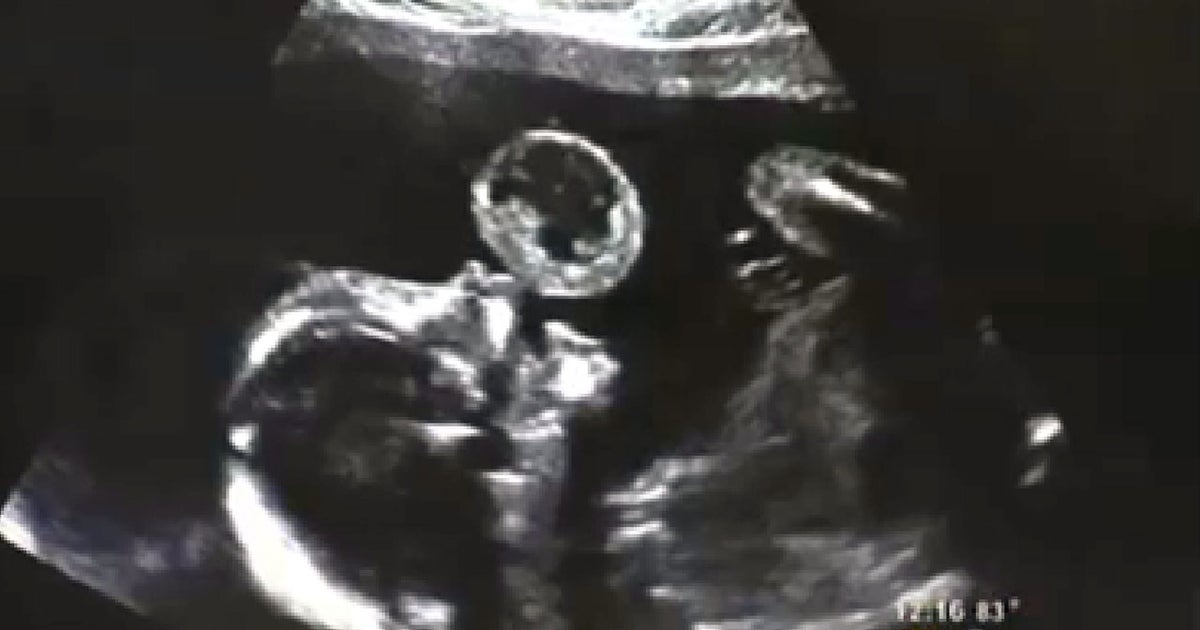

From www.cbsnews.com

Miami doctors remove tennis ballsized tumor from fetus' mouth in Tennis Ball Size Brain Tumor The tumor was connected to my main brain stem and pushed its way up. After spending a few nights in icu i was told the. Ruth stevens was shocked to learn she had a tumor in her brain the size of a tennis ball. This got me a ride in a magnetic resonance imaging machine, which revealed a brain mass. Tennis Ball Size Brain Tumor.